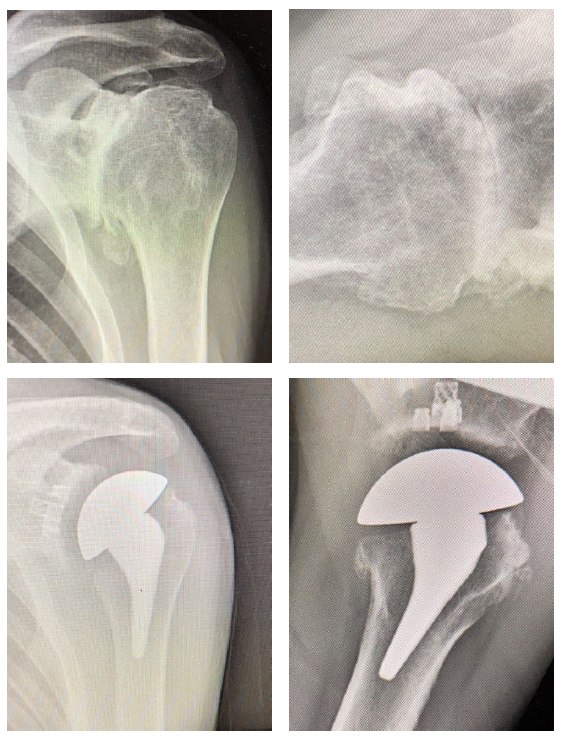

Patient 1: Primary anatomic total shoulder arthroplasty using Equinoxe Preserve short stem and caged glenoid.

- Active male in his 60s, retired reporter with surprisingly good preop motion

- This patient is a good candidate for either a stemless anatomic or a short stem anatomic

- Six (6) weeks postop his external rotation (ER) has returned to preop baseline of 45 degrees, and his forward flexion (FF) has improved from 90 to 145 degrees.

Patient 2: Primary anatomic total shoulder arthroplasty using a stemless implant.

- Active male in his 60s, retired radiologist

- Typical pain and significant range of motion limitations

Patient 3: Revision of a failed anatomic total shoulder with loose humeral stem to reverse total shoulder arthroplasty

- The humeral stem was loose, so it was replaced with the short stem for the aggressive proximal geometry, which fit nicely and improved the proximal press-fit

- Revised an anatomic to a reverse, replacing stem from another company

- Significant glenoid wear led to augmented baseplate choice – superior posterior augment

Patient 1: 59-year-old male with avascular necrosis of the humeral head.

- Left primary anatomic total shoulder arthroplasty using Equinoxe Preserve short stem and cage glenoid.

Patient 3: 74-year-old female with cuff tear arthropathy.

- Right primary reverse shoulder arthroplasty with augmented baseplate to treat glenoid wear.

Patient 4: 63-year old male with osteoarthritis.

- Left primary anatomic total shoulder arthroplasty using Equinoxe Preserve short stem with 8-degree cage glenoid.